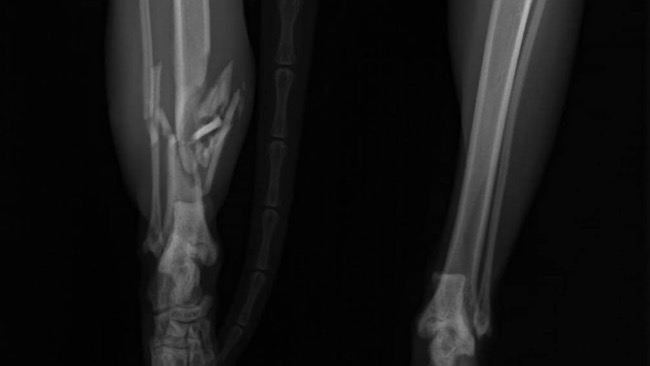

Jej łapka jest złamana, mamy szansę ją uratować by mogła odzyskać sprawność - potrzebna jest pilna operacja.

Łapa Bajki wisi bezwładnie od kolana w dół. Konieczne jest ustabilizowanie jej na płytce.